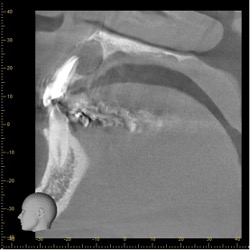

右下と左下の欠損部にはインプラント治療をご希望されました。また上あごの前歯が割れており、膿がたまって骨が大きく溶けてしまっていたため、抜歯を行いブリッジ治療を施しました。

ブリッジの素材は金属を使わないジルコニアという虫歯になりにくい素材を用いて治療させていただきました。

【術前の前歯のCT写真】↓骨が大きく溶けているのがわかります。